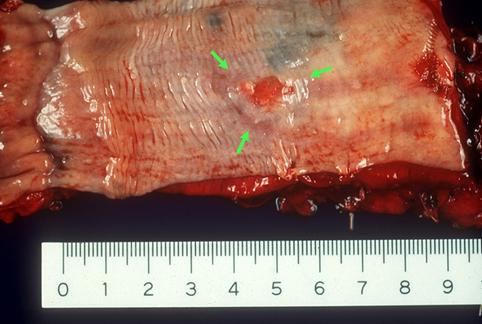

질환(병리주체)의 분류 악성 상피성종양/편평상피암

부위(장기별) 식도/중

검사방법 마크로

종양의 육안분류 0형(표재형)/I형(Isp)

종양의 최대경(밀리미터) 15~19

종양의 심달도 sm